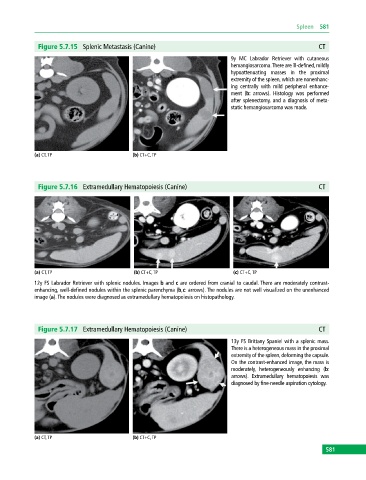

Figure 5.7.15 Splenic Metastasis (Canine) CT

9y MC Labrador Retriever with cutaneous

hemangiosarcoma. There are ill‐defined, mildly

hypoattenuating masses in the proximal

extremity of the spleen, which are nonenhanc

ing centrally with mild peripheral enhance

ment (b: arrows). Histology was performed

after splenectomy, and a diagnosis of meta

static hemangiosarcoma was made.

(a) CT, TP (b) CT+C, TP

Figure 5.7.16 Extramedullary Hematopoiesis (Canine) CT

(a) CT, TP (b) CT+C, TP (c) CT+C, TP

12y FS Labrador Retriever with splenic nodules. Images b and c are ordered from cranial to caudal. There are moderately contrast‐

enhancing, well‐defined nodules within the splenic parenchyma (b,c: arrows). The nodules are not well visualized on the unenhanced

image (a). The nodules were diagnosed as extramedullary hematopoiesis on histopathology.

Figure 5.7.17 Extramedullary Hematopoiesis (Canine) CT

13y FS Brittany Spaniel with a splenic mass.

There is a heterogeneous mass in the proximal

extremity of the spleen, deforming the capsule.

On the contrast‐enhanced image, the mass is

moderately, heterogeneously enhancing (b:

arrows). Extramedullary hematopoiesis was

diagnosed by fine‐needle aspiration cytology.